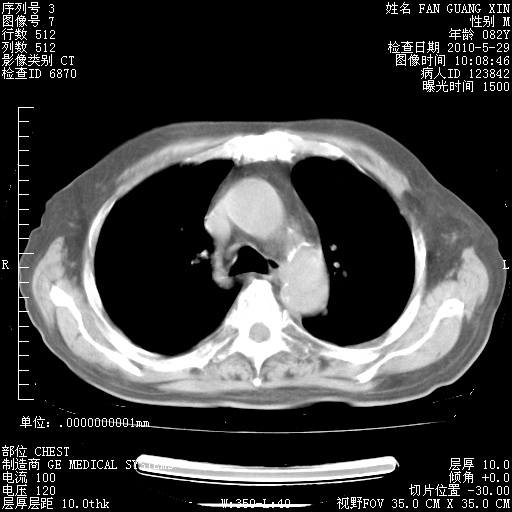

还需要哪些辅助检查?我们医院排除真菌感染没有任何检验方法,胸片好像能够排除肺部真菌感染。